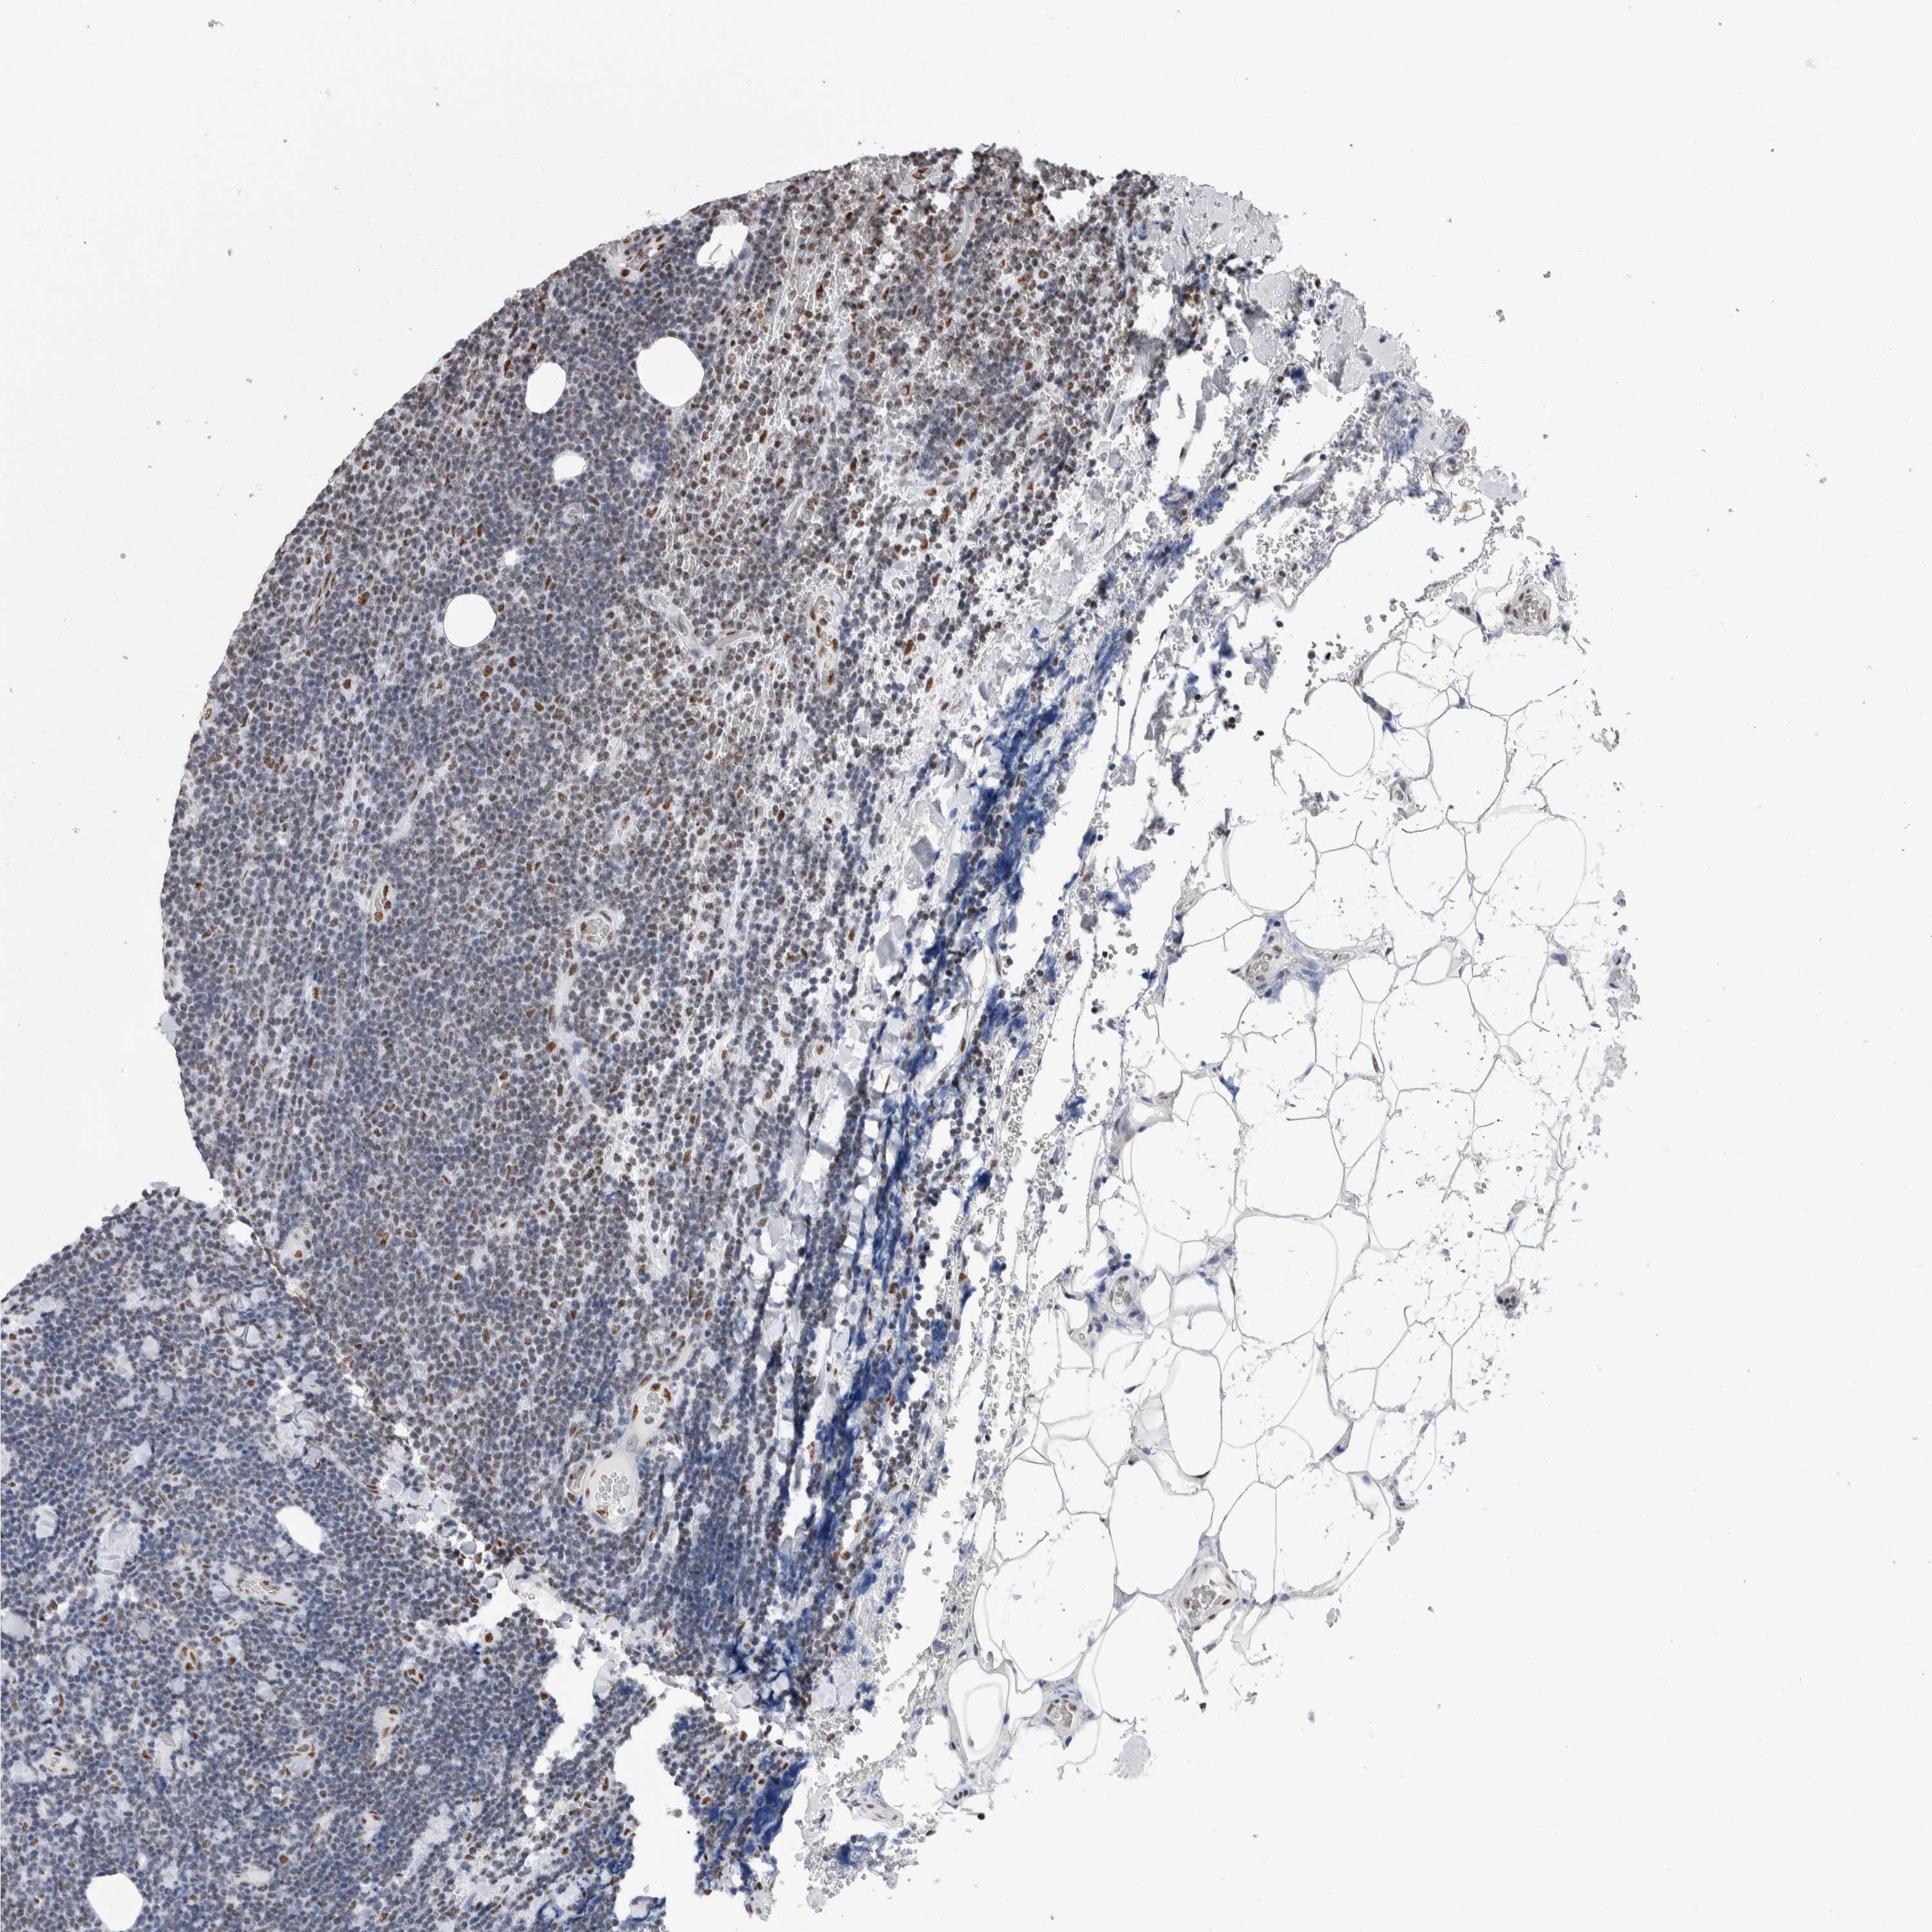

LYMPHOMA - Protein expressioni

A mouse-over function shows sample information and annotation data. Click on an image to view it in a full screen mode. Samples can be filtered based on level of antibody staining by selecting one or several of the following categories: high, medium, low and not detected. The assay and annotation is described here.

Antibody stainingi

Antibody staining in the annotated cell types in the current human tissue is reported as not detected, low, medium, or high, based on conventional immunohistochemistry profiling in selected tissues. This score is based on the combination of the staining intensity and fraction of stained cells.

Each image is clickable and will lead to virtual microscopy that enables deeper exploration of all samples and also displays staining intensity scores, fraction scores and subcellular localization as well as patient and tissue information for each sample.

Antibody HPA026558

Staining

High

Medium

Low

Not detected

Intensity

Strong

Moderate

Weak

Negative

Quantity

>75%

75%-25%

<25%

None

Location

Nuclear

Cytoplasmic/membranous

Cytoplasmic/membranous,nuclear

Hodgkin's disease, NOS

Malignant lymphoma, non-Hodgkin's type, High grade

Malignant lymphoma, non-Hodgkin's type, Low grade